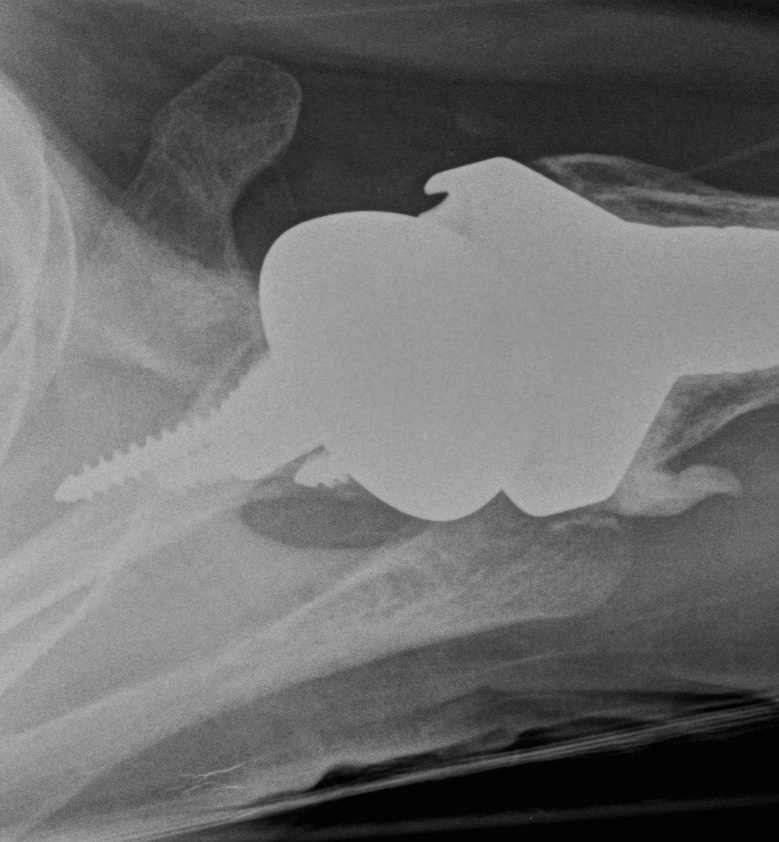

Centering guide wire passed

Depuy Synthes Delta Xtend

Center of inferior circle of glenoid

- metaglene needs to be positioned low to prevent inferior impingement and dislocation

- wire needs to angle perpendicular or slightly inferior / avoid superior tilt

- should exit scapula anteriorly about 3cm medial to glenoid

- ensure inferior screw will be in inferior good bone

Metaglene / baseplate fixation

Screws as long as possible

- inferior screw - long into scapular pillar

- superior screw - aim for coracoid

- anterior / posterior screws - convergent / divergent

Glenosphere

Typically lateralized / slight inferior overhang